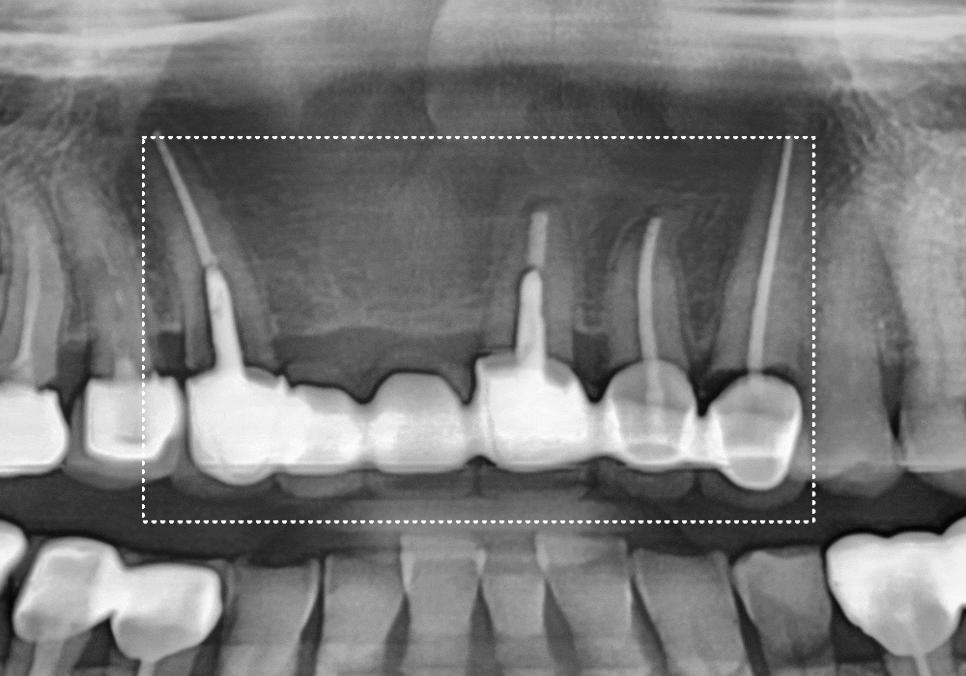

입안을 살펴보니, 오른쪽 앞니(#11)는

이미 부러져서 뿌리만 남은 상태였고,

왼쪽 앞니(#21)는 동요도 3도로

확인될 만큼 심하게 흔들리고 있었습니다.

240523

치과에서 말하는 동요도 3 도는

치아가 앞뒤와 좌우뿐만 아니라,

위아래(수직)로도 쑥쑥 들어갔다

나올 정도로 심하게 흔들리는 상태를 말해요.

뿐만 아니라 충치도 꽤 깊게 진행 중이였어요.

230524

잇몸뼈가 치아를 거의

잡아주지 못하는 단계라

뿌리만 남은 치아와 흔들리는 치아 모두

발치가 불가피했습니다.

환자분의 경우 빠진 치아 옆 치아마저(#12)

약간 흔들리고 있어서,

브릿지로 하기엔 무리가 있었어요.